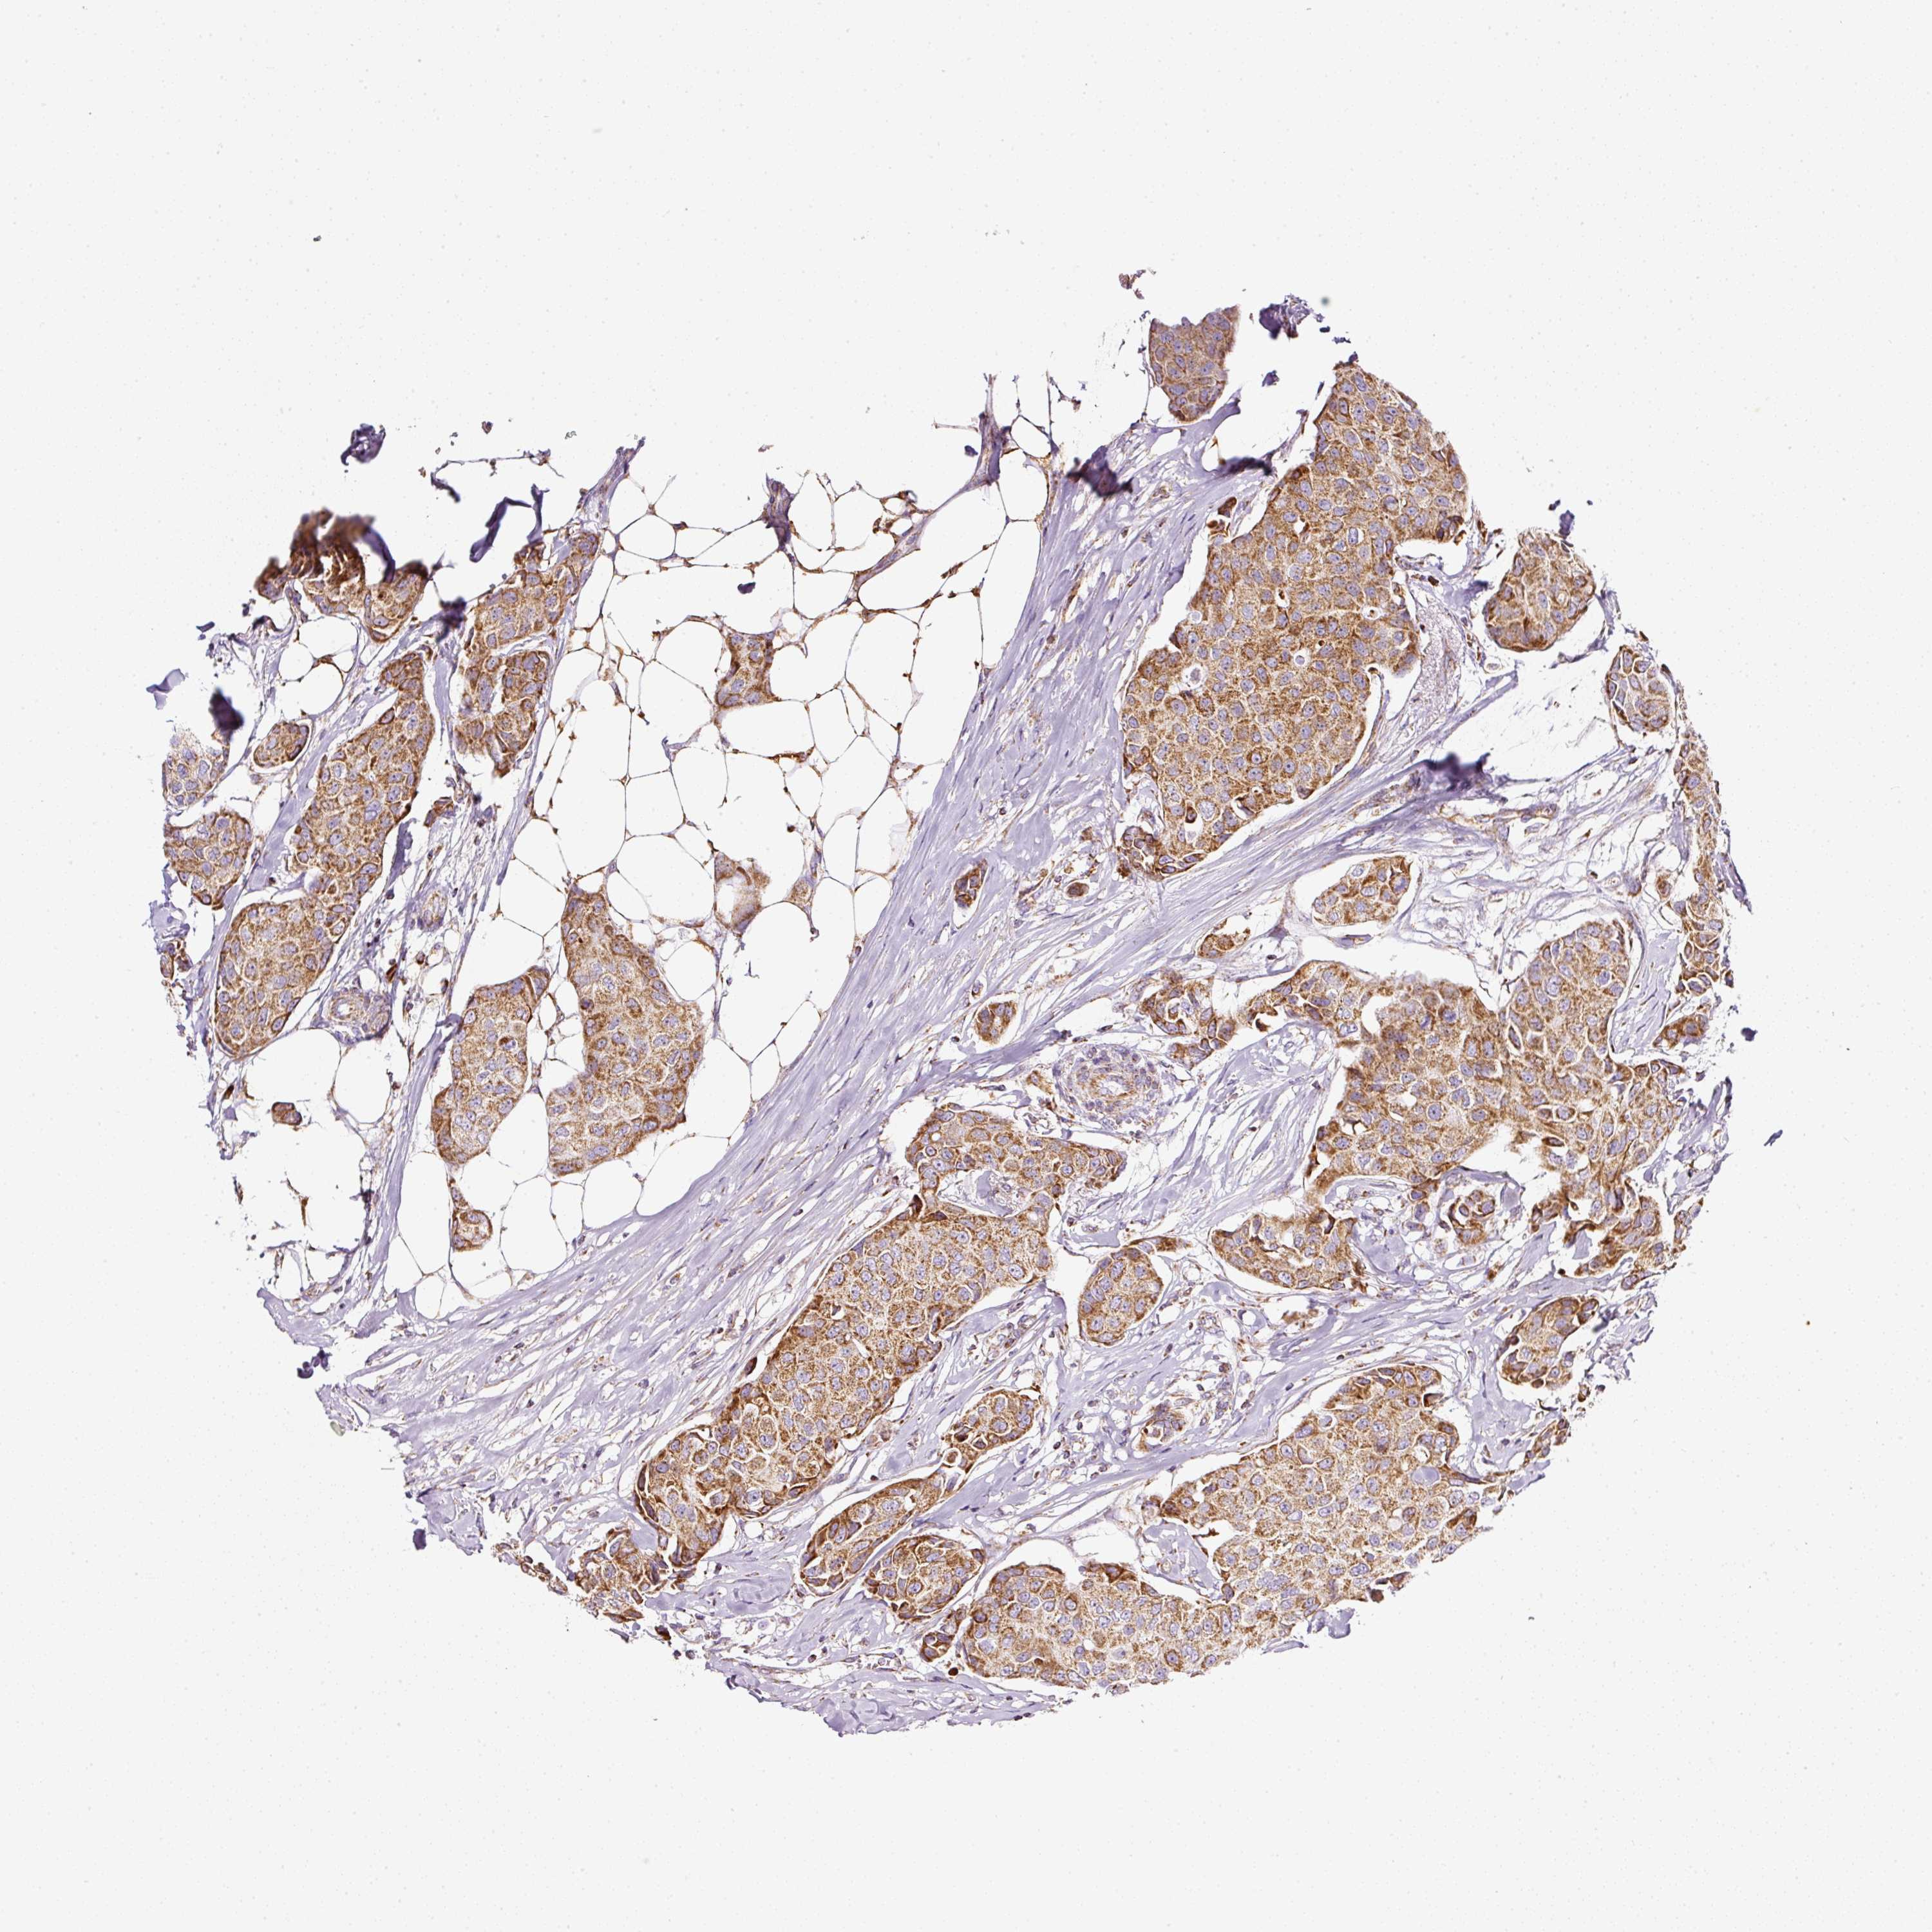

CANCER BREAST CANCER Show tissue menu

BRCA TCGA BRCA VALIDATION PROTEIN EXPRESSION